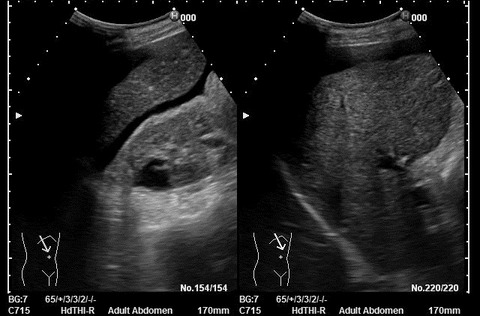

C-1 肝硬変

[超音波検査所見]

肝臓:表面は軽度の凹凸不整を呈し、実質エコーは軽度粗雑化を認める。右葉は軽度萎縮を呈し、辺縁の鈍化を認める。

肝臓周囲には腹水貯留を認める。

脾臓:腫大を認める。(千葉大第一内科の式:7.2cm×5.4cm=38.8㎠)脾静脈の拡張は認めず。

肝臓や脾臓周囲に腹水貯留を認める。

門脈圧亢進所見や、リンパ節の腫大は認められなかった。

エコー図